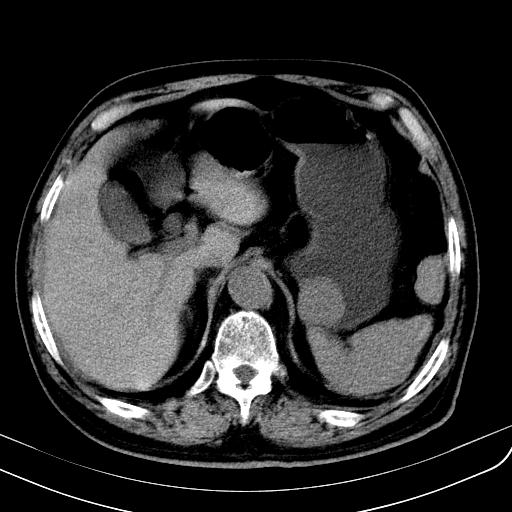

胃底靠近胃大弯处可见一圆形软组织影,直径为3.45cm,ct值约为30.1hu

边缘光滑,密度均匀,良性占位,首先考虑平滑肌瘤。

边缘光滑,密度均匀,良性占位,首先考虑平滑肌瘤。其实平滑肌瘤也是间质瘤的一种

考虑胃底平滑肌瘤。血肿不除外。